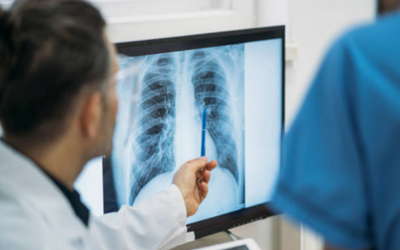

Chest X-ray

A chest X-ray aids in the estimation of the size of the heart and the lung status, since large ASDs may cause a volume load to the lungs.